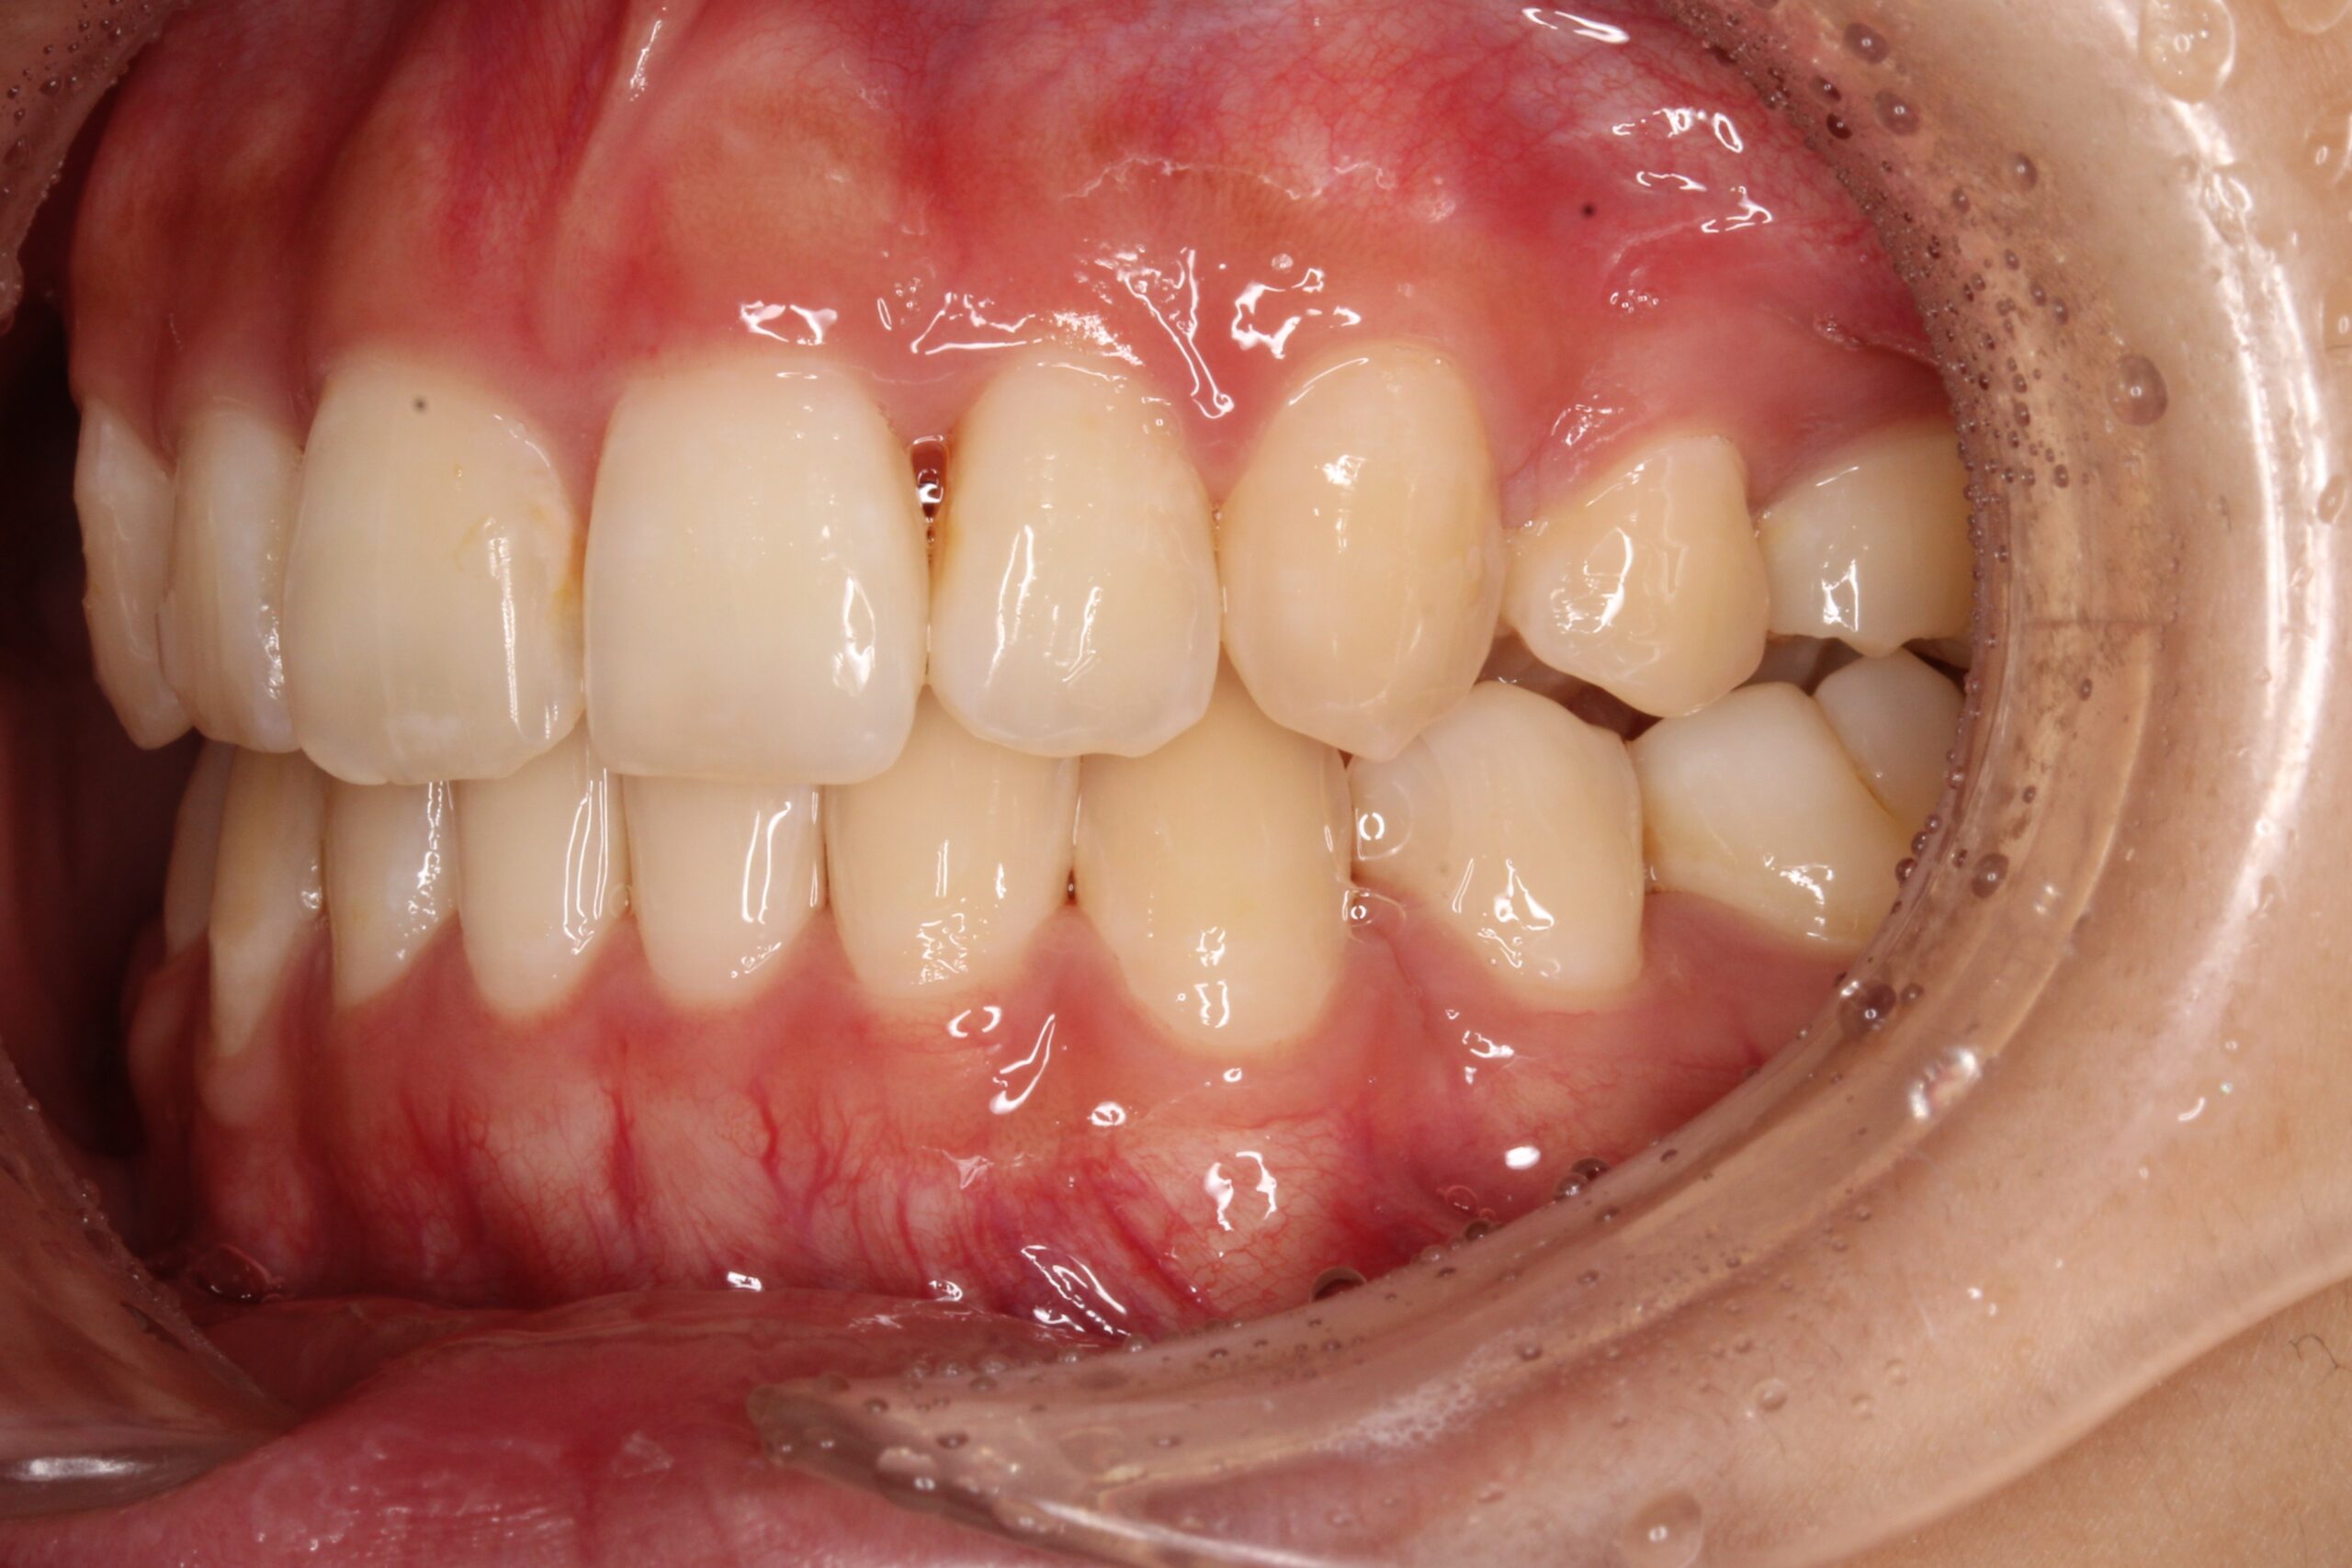

矯正術前:正面

矯正術後:正面